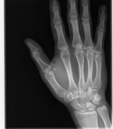

Broken Hand

This was just a hairline fracture that I managed to get from a soccer game. I thought it was pretty cool that I was given all of the digital copies.

Broken Hand (264472)